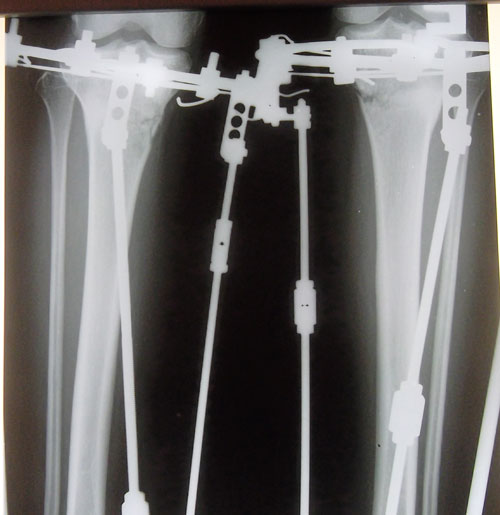

Наталья, большое спасибо за совет!!!Sekretar Onipko писал(а):Девочки, слушайте всегда внимательно! Размягчают корочки перекисью водорода 3%, а не спиртом. Спирт сушит и дубит кожу. http://klinika-onipko.kz/forums/viewtop ... f=27&t=121Сначала я размягчила все корочки смоченным в спирте бинтом, прям обильно смачивала и накладывала на спицы! Очень очень осторожно все-все корочки убрала. Не отдирайте корочки, а то может закровить, а это воспаление, инфекция и тд... Лучше еще раз спиртом смочить, размягчить.

Хлорфиллипт применяют при покраснении места вокруг спиц, для профилактики воспаления.

За неимением перекиси пришлось размягчать спиртом, перекись приобретена, буду размягчать ей!